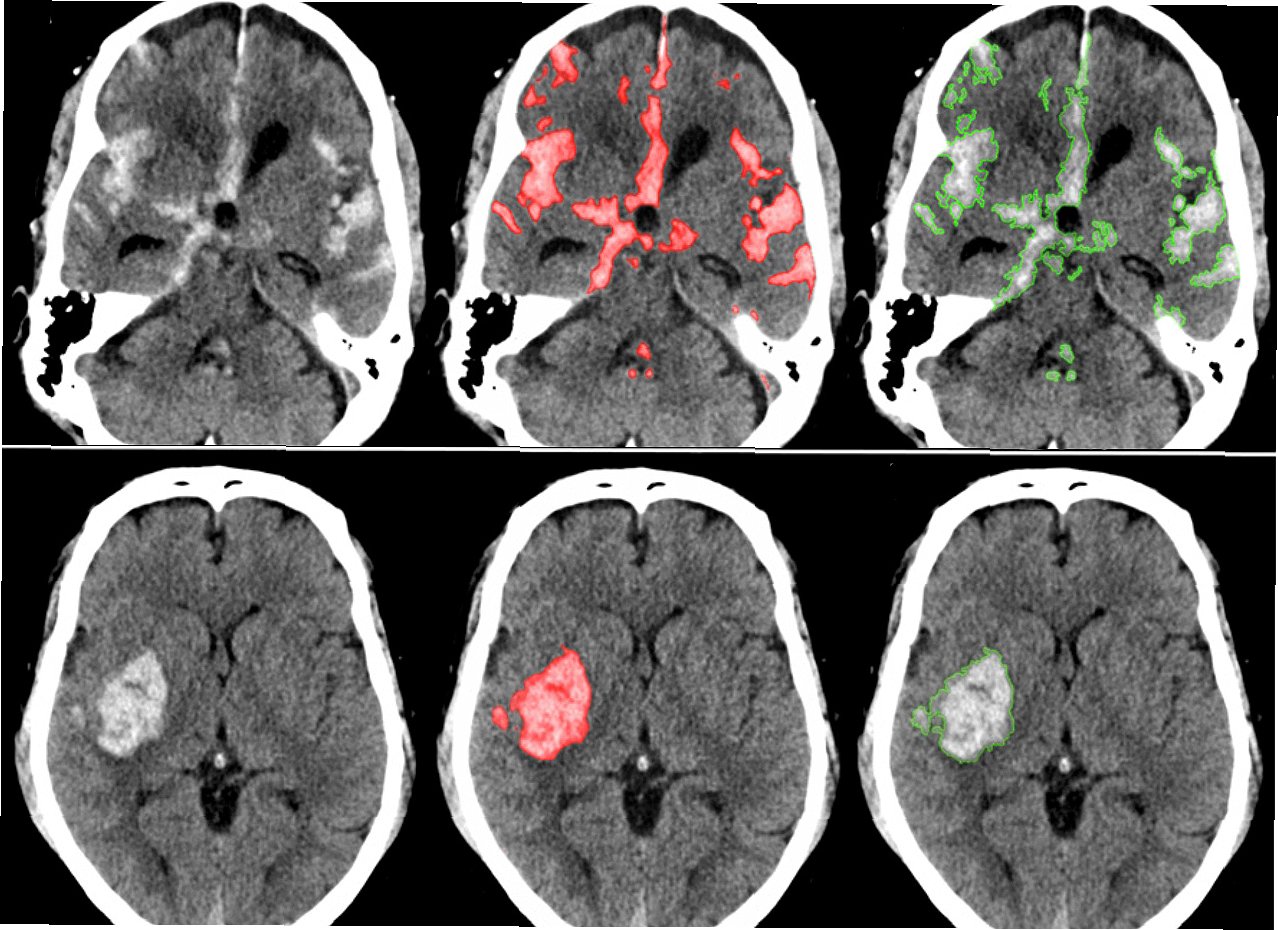

AI 기술은 뇌졸중 진단 분야에서 괄목할 만한 발전을 이루고 있습니다. 특히 영상 분석 기술을 통해 CT, MRI 등의 뇌 영상 데이터를 빠르고 정확하게 분석하여 뇌출혈, 뇌경색의 위치와 범위를 파악할 수 있습니다. AI는 뇌졸중의 골든 타임을 확보하는 데 기여하며, 의료진의 진단 정확도를 향상시키고, 환자 맞춤형 치료 계획을 수립하는 데 도움을 줍니다. AI 기반의 진단 시스템은 응급 상황에서 의료진의 의사 결정을 돕고, 환자의 생존율을 높이는 데 기여할 수 있습니다. AI는 뇌졸중 환자의 초기 진단뿐만 아니라, 재발 위험을 예측하고 예방하는 데에도 활용될 수 있습니다. AI 기술의 발전은 뇌졸중 진단 분야의 혁신을 넘어, 의료 서비스의 질을 전반적으로 향상시키는 데 기여할 것입니다. AI는 방대한 양의 의료 데이터를 학습하고 분석하여, 인간의 한계를 뛰어넘는 정확도와 효율성을 보여줍니다. AI 기술은 뇌졸중 환자의 생존율을 높이고, 삶의 질을 개선하는 데 중요한 역할을 할 것입니다.